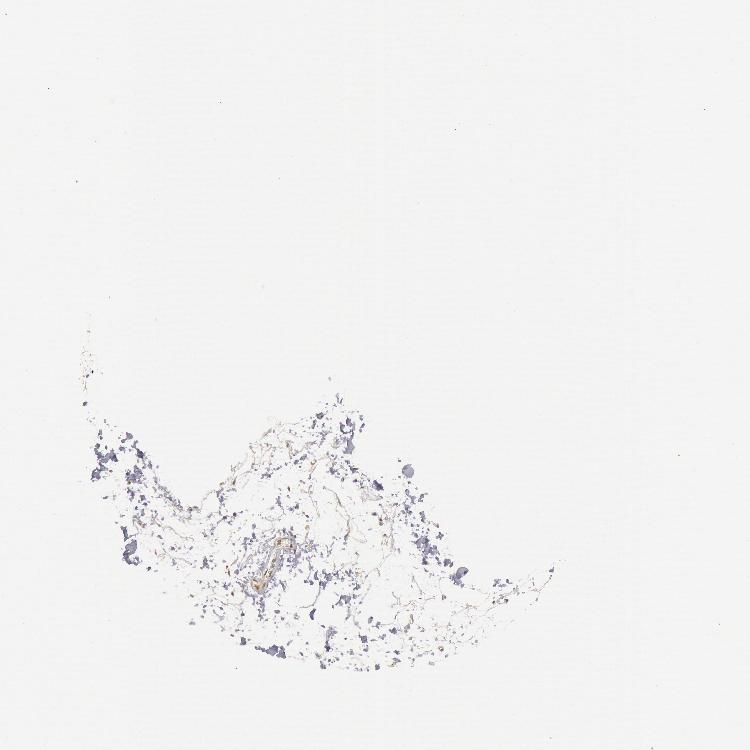

SOFT TISSUE 2 - Antibody stainingi

Antibody staining in the annotated cell types in the current human tissue is reported as not detected, low, medium, or high, based on conventional immunohistochemistry profiling in selected tissues. This score is based on the combination of the staining intensity and fraction of stained cells.

Each image is clickable and will lead to virtual microscopy that enables deeper exploration of all samples and also displays staining intensity scores, fraction scores and subcellular localization as well as patient and tissue information for each sample.

Antibody HPA001306Antibody CAB033665

Fibroblasts -Not detected

Peripheral nerve Not detectedMedium